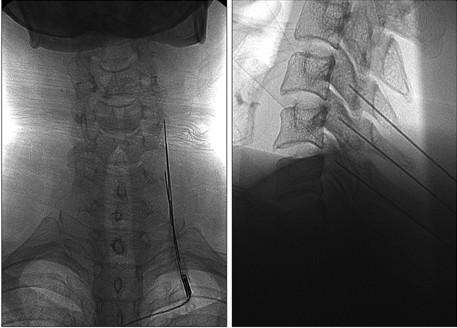

Ao lado, mostra-se uma imagem de Raio-X com a correta colocação das agulhas na saída do ramo medial que deve ser confirmada antes de iniciar a lesão térmica.

Na coluna cervical, o procedimento é parecido, mudando apenas as ponteiras, que são menores. Ao lado, exemplo de rizotomia cervical pelo Raio-X.